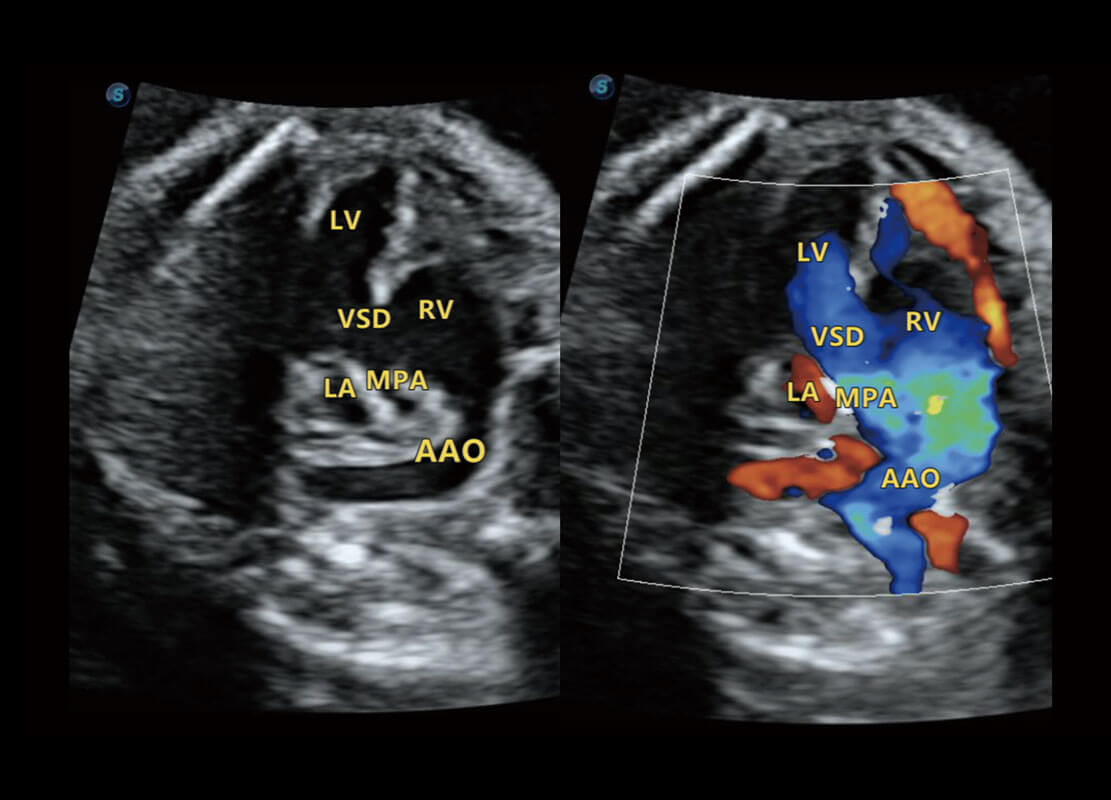

P60搭载一系列胎儿心脏成像技术,实现精细的胎儿心脏评估。

右室双出口

胎心容积成像